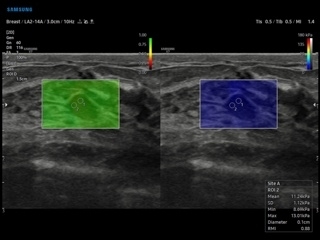

- Эластография: Elastoscan, E-Strain, E-Cervix;

- S-Detect для молочной железы и щитовидной железы;

- Elastoscan — программы эластографии для исследований щитовидной железы, молочной железы у женщин и предстательной железы у мужчин;

- E-Strain — полуколичественный анализ индекса Strain Ratio в режиме компресионной эластографии;

- S-Shearwave imaging — программа цветовой сдвиговой эластографии позволяющая автоматически определять индекс жесткости различных участков исследуемого объекта в кПа или м/с, получая при это еще и индекс достоверности данных RMI;

- S-Detect Breast — программа автоматического обнаружения и анализа образований молочной железы у женщин, измерение и классификация по системе BI-RADS;